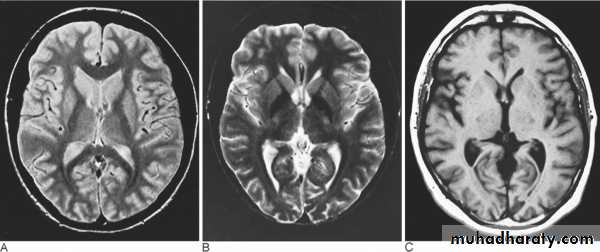

Patient with multiple sclerosis with plaques of demyelination shown on (A) fast spin-echo (FSE) proton density; (B) FSE T2; and (C) FSE FLAIR. There is no discernible abnormality on T1-weighted images without contrast